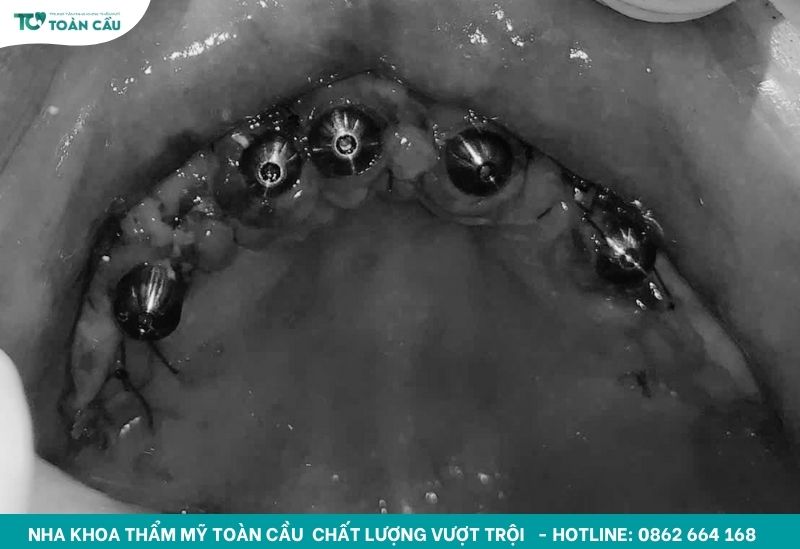

Trong phác đồ, bước đầu tiên là điều trị dứt điểm viêm nha chu để tạo môi trường lành mạnh trước khi cấy trụ. Sau đó, bác sĩ tiến hành cấy implant cho cả hai hàm với tổng cộng 10 trụ, trong đó có 2 trụ gò má để tăng độ neo giữ ở vùng xương yếu. Tiếp theo, chú được gắn răng tạm thẩm mỹ để có thể ăn nhai và sinh hoạt bình thường trong thời gian chờ trụ tích hợp hoàn toàn với xương hàm.